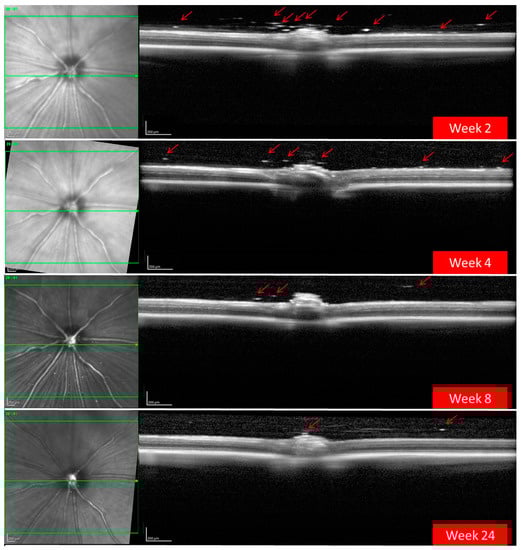

A total of 186 OCT videos from 43 treated rats (43 hypertensive REs treated with BRI/LAP IF and 29 non-treated hypertensive LEs) and 23 non-treated healthy rats (23 REs/23 LEs) were analysed. The REs injected with the BRI/LAP IF showed hyperreflective dots/aggregates mixing uniformly in the vitreous gel and dispersed as floaters, with a tendency to move toward the vitreoretinal interface during the 24-week follow-up [9]. There was also OCT-guided evidence of the hyperreflective dots crossing the vitreoretinal interface and embedding deeply in the retinal tissue. Particular qualitative characteristics of the behaviour of the BRI/LAP IF observed in several animals are shown in Figure 2.

OCT also detected a progressive decrease over time in the number and size of BRI/LAP aggregates (Figure 3). Figure 4 shows the temporal change in aggregate size. Figure 4A shows that total aggregate area decreased with time over the 24 weeks of follow-up. This drop was very marked during the first 4–6 weeks, after which the change was more gradual. Moreover, total aggregate area increased two weeks after injection. Although a similar trend was observed (aggregate size increased at 2 weeks), this seems to be at the expense of an increase in mean aggregate size. A considerable decrease was then detected around 8 weeks, and from 12 weeks onwards mean aggregate size remained practically constant (Figure 4B).

For the formulation injected into the vitreous to reach the retinal cells (and exert its effect), it must pass through the posterior vitreous cortex (PVC) as well as the ILM, which has pores measuring 10–20 nm. OCT showed hyperreflective aggregates capable of traversing the PVC and ILM and reaching the intraretinal space, possibly by diffusion (Figure 2) due to the small size of the Laponite platelets (1 nm high, 30 nm diameter) [6] and the lipophilicity of brimonidine. In this regard, various authors also found internalisation of drug delivery systems in the retina. Koo et al. [28] described the passage of intravitreal nanoparticles through the retina by both diffusion and endocytosis by the Müller cells, and Xu et al. [29] found that cationic amphiphilic intravitreal polymers reached RPE cells. The space between the ILM and the PVC houses an interdigitate extracellular matrix [15]. In this space, the authors observed that the BRI/LAP IF arranged itself in a row with the aggregates ordered one after the other at different heights, concentrically (see Figure 2A,C and Figure 6). This arrangement is similar to that proposed in the formation of Laponite film, [30] exhibiting a side-by-side arrangement of the Laponite platelets and subsequent stacking of them in different layers. This arrangement is favoured by several film-forming methods, including the Langmuir–Blodgett method, in a liquid–solid interface similar to the vitreous–retina interface, and even more so in the case of hybrid films with organic molecules and macromolecules [31].

Figure 3. Progressive decrease in hyper-reflective aggregates (red arrows) of the brimonidine–Laponite intravitreal formulation (BRI/LAP IF) detected in the vitreous–retinal interface using optical coherence tomography over 24 weeks of follow-up.